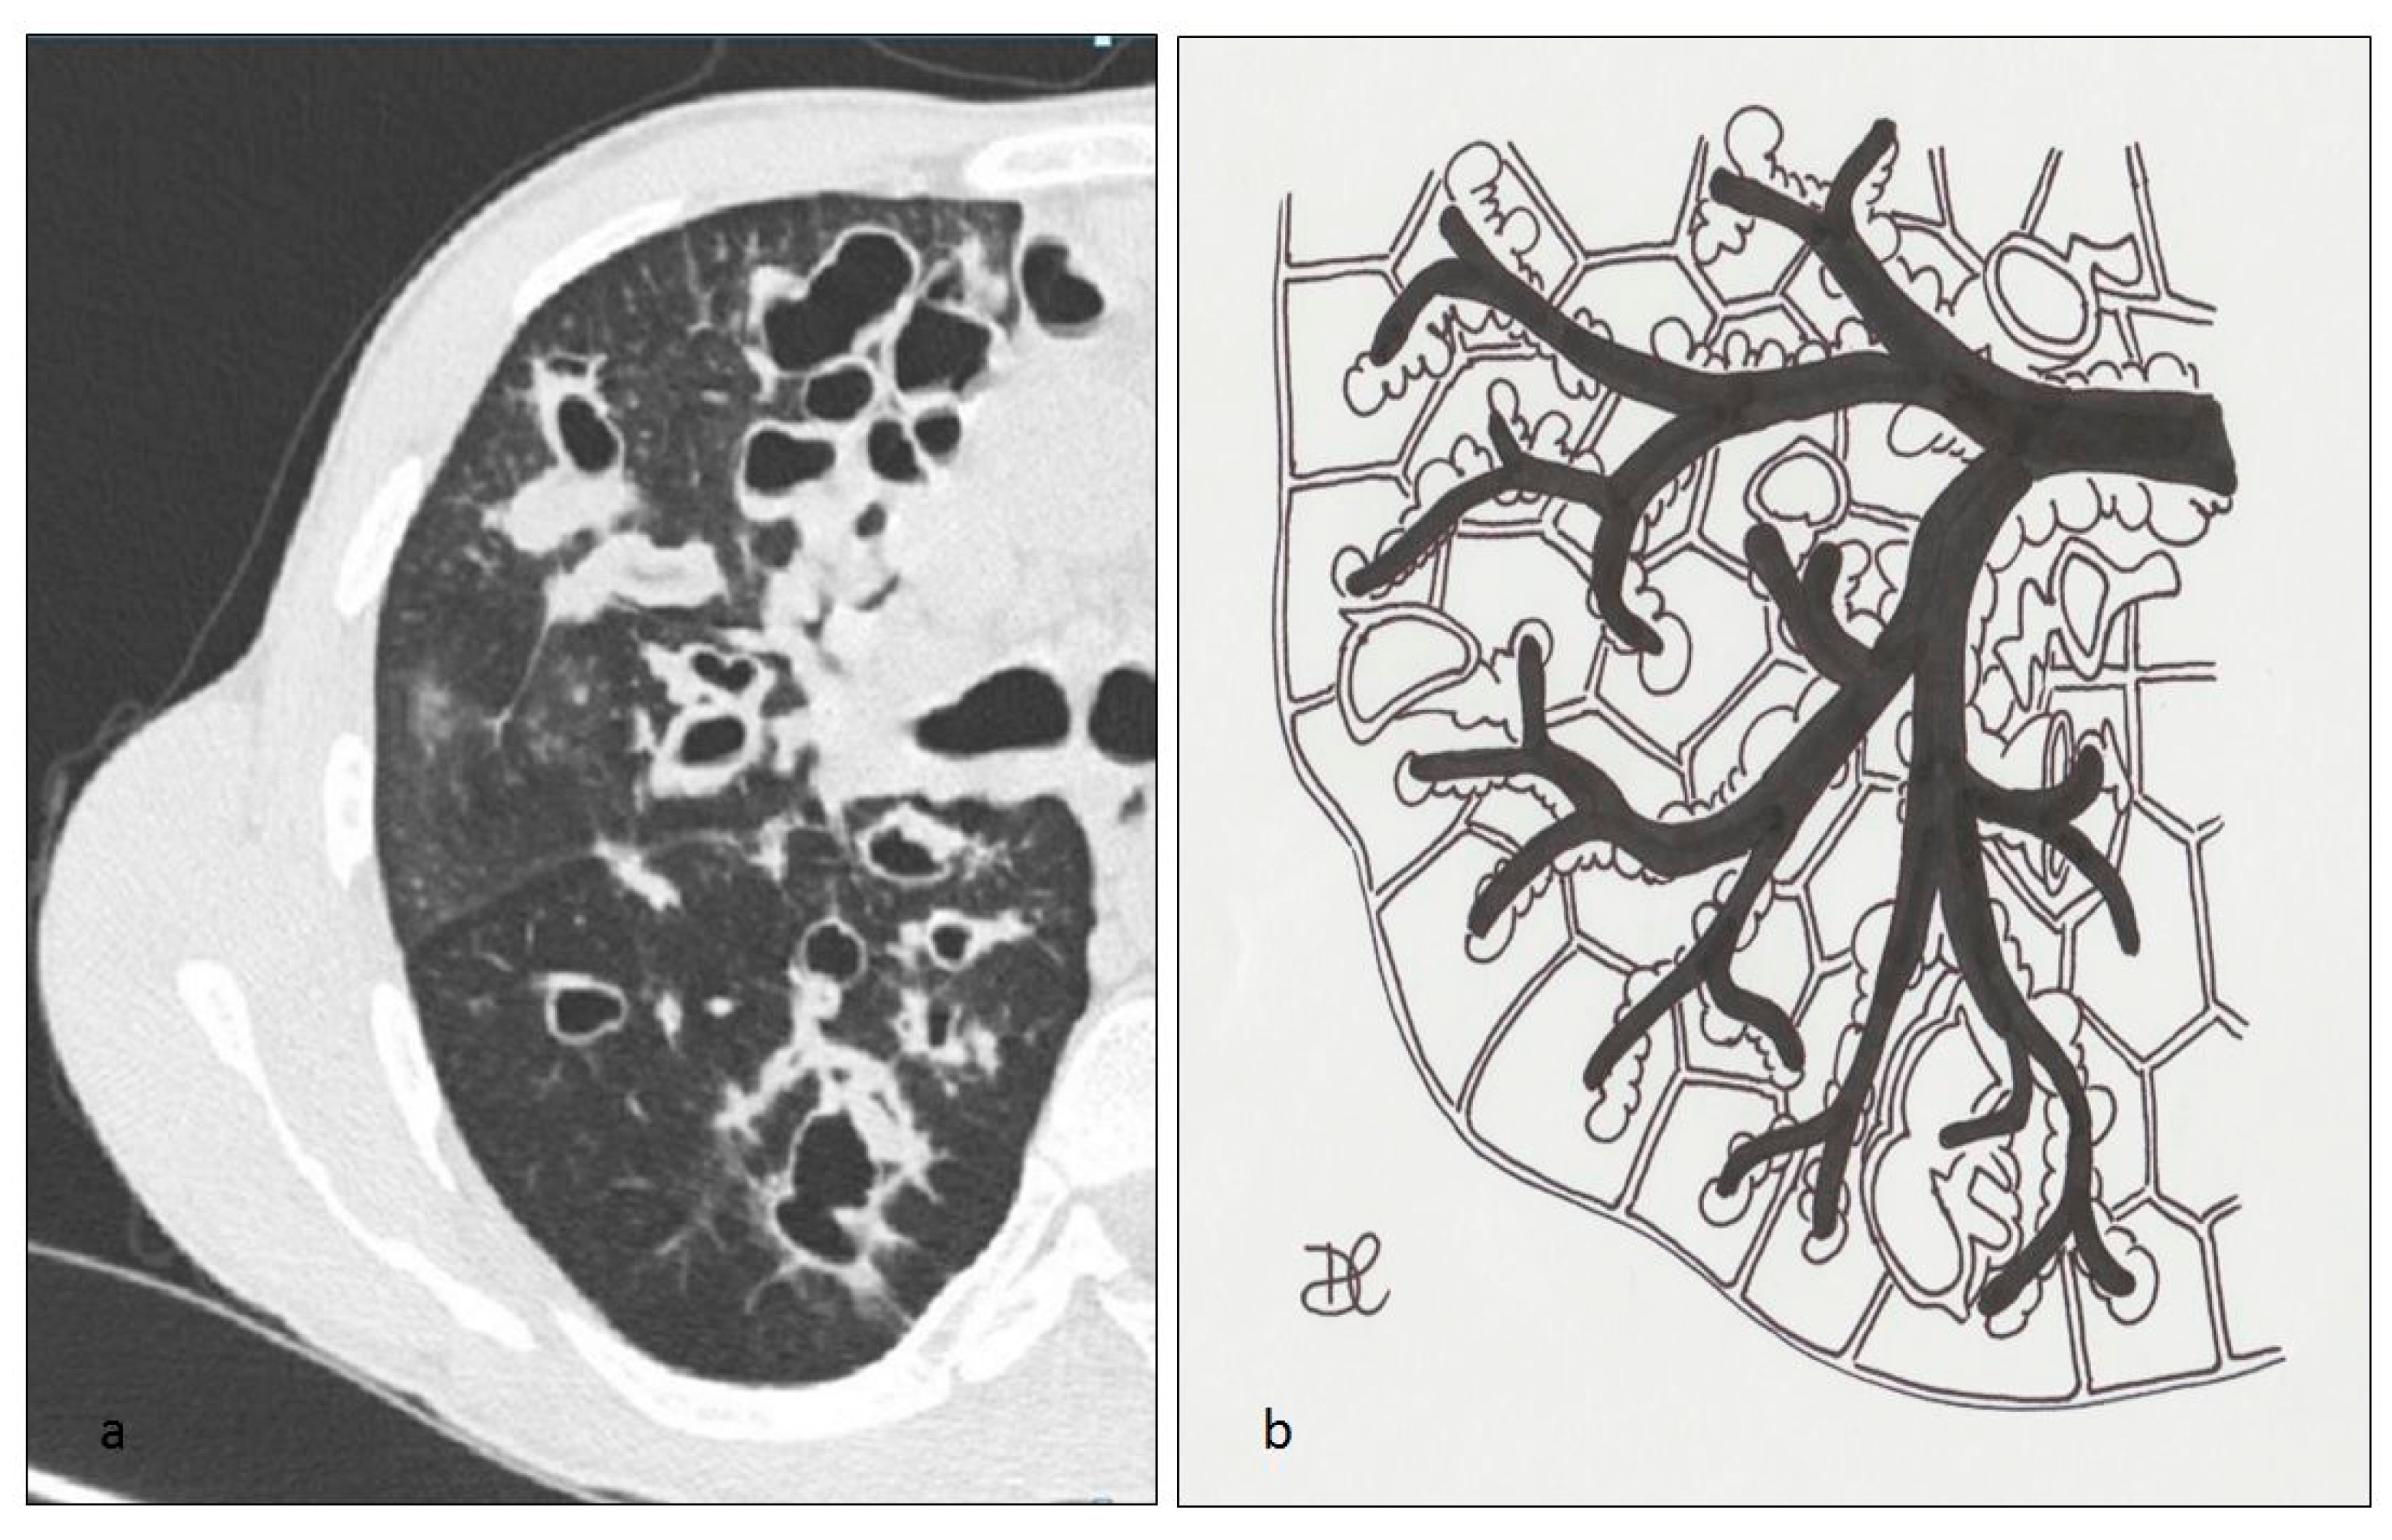

Figure 17. Cystic fibrosis (CF) pattern (a), multiple cystic lesions, represented by cystic bronchiectasis, filled by mucous secretion, abscess cavities or bullae, mainly located in subpleural and upper zones of the lung; these bronchiectases may be variable in size, with regular shape, wide distribution and thickened walls (b).

Radiologically, lung involvement consists of multiple cystic lesions—due to cystic bronchiectases, filled by mucous secretion—associated with the development of abscess cavities or bullae, mainly located in subpleural and upper zones of lungs [61]; in addition, tree-in-bud pattern with mosaic perfusion and focal air-trapping areas on expiratory scans may be depicted, due to the presence of an obstructive disease of small airways [62] (Figure 17 and Figure 18). Mediastinal lymphatic nodes enlargement, pleural thickening and pulmonary artery dilatation may be also appreciated on HRCT images.